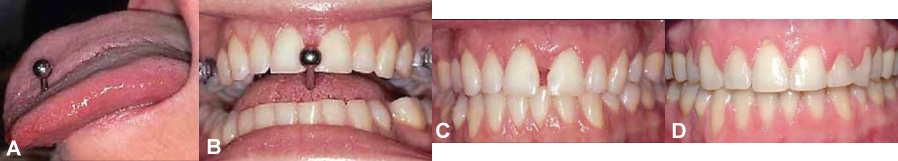

Autres exemples de piercing de la langue et de la lèvre.

(A) Perçage de la langue avec une tige “haltère”. (B) La patiente a développé l’habitude d’appuyer la tige contre ses dents. (C) Les centrales se sont déplacées et un espace important s’est créé. (D) Une correction orthodontique a été nécessaire pour refermer l’espace. (ill.; Tabbaa, JCO 2010)